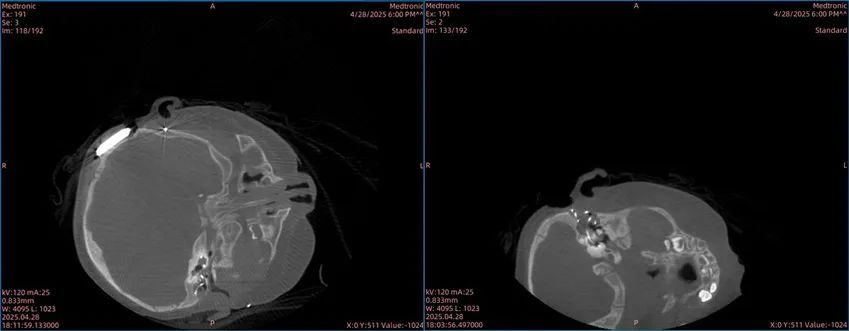

71岁的山东老先生在7年前,因终末期心力衰竭做了心脏移植,需终身服用免疫抑制剂防止排斥反应,还患有2型糖尿病。2024年底体检,他被查出升结肠癌、直肠癌(双原发)、肝左外叶两处转移灶,还有胆囊结石伴慢性胆囊炎,肿瘤标志物猛升,病情危急。经当地医生推荐,他慕名来到2026年足球世界杯直播附属华山医院胃肠外科主任医师蒿汉坤的门诊。

麻醉团队精心设计方案,手术中全程监测患者心脏功能。蒿汉坤团队仅用3小时10分钟,就顺利完成肝左外叶切除、胆囊切除、右半结肠切除、直肠前切除4项高难度手术。手术没有大切口,腹部取标本切口仅5厘米,切除标本最大长径20厘米,出血不到50毫升,术后也没留胃管或肛管。

术后管理同样关键。针对老人的免疫抑制状态,专家们精细调整了抗肿瘤、抗感染和营养支持方案。在护理团队管理下,老人术后第1天就能饮水、在床上活动,第2天排气后下床,第3天流质饮食,第7天正常排便,第8天顺利出院。